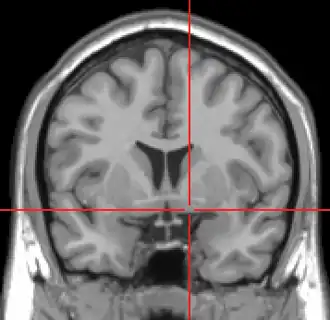

![]() Intermediate magnification micrograph of the nucleus basalis. LFB-HE stain. | |

The nucleus basalis in humans is a somewhat diffuse collection of large cholinergic neurons in the basal forebrain.[2] The main body of the nucleus basalis lies inferior to the anterior commissure and the globus pallidus, and lateral to the anterior hypothalamus in an area known as the substantia innominata.[1] Rostrally, the nucleus basalis is continuous with the cholinergic neurons of the nucleus of the diagonal band of Broca.[1] The nucleus basalis is thought to consist of several subdivisions based on the location of the cells and their projections to other brain regions.[2] Occasional neurons belonging to the nucleus basalis can be found in nearby locations such as the internal laminae of the globus pallidus and the genu of the internal capsule.[1]